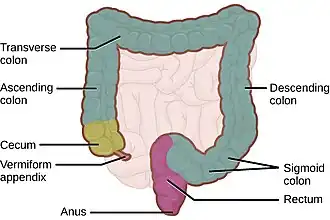

Толстая кишка, обозначены: розовым — червеобразный отросток, оливковым — слепая кишка, серым — ободочная кишка, фиолетовым — прямая кишка, светлобежевым на заднем фоне — петли тонкой кишки | |

В толстой кишке человека анатомически выделяют следующие отделы:

- слепая кишка (лат. caecum) с червеобразным отростком (лат. appendix vermiformis);

- ободочная кишка (лат. colon) с её подотделами:

- восходящая ободочная кишка (лат. colon ascendens);

- поперечная ободочная кишка (лат. colon transversum);

- нисходящая ободочная кишка (лат. colon descendens);

- сигмовидная ободочная кишка (лат. colon sigmoideum);

- прямая кишка, (лат. rectum), с широкой частью — ампулой прямой кишки (лат. ampulla recti), и оконечной сужающейся частью — заднепроходным каналом (лат. canalis analis), которая заканчивается анусом (лат. anus).